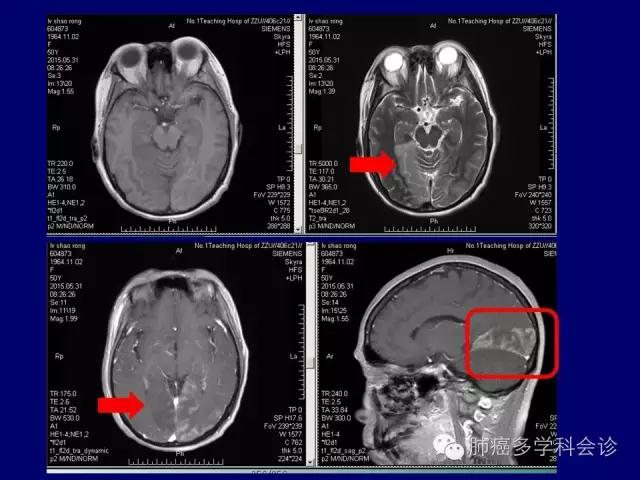

症状不突出,体检时发现 IV 期

胸水中诊断:常规病理 + 分子病理(ventana IHC)